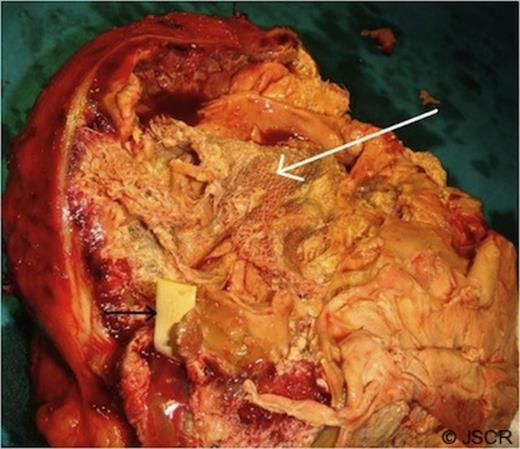

A radio-opaque material was seen in the lesion raising the suspicion of a foreign body. Common bile duct was dilated and contained a stone which was removed endoscopically. At exploration, a large globular lesion was found which was densely adhered to the adjacent structures (anterior abdominal wall, omentum, transverse colon, and antrum of the stomach). En-bloc resection of the mass along with the adhered transverse colon was done (Figure-2). Cut section of the mass showed a large surgical sponge and a foreign body within it (Figure-3).The patient had an uneventful recovery and she was well at 19-month follow-up.

Operative photograph showing a large mass (white arrow) with adherent transverse colon (black arrow).